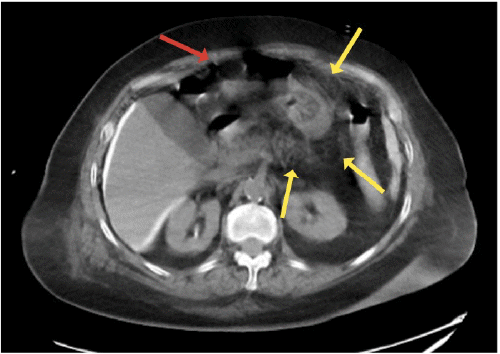

One hour after initiating PEG tube feeds, the patient developed pain, flushing, and emesis. Tube feeds were immediately discontinued due to clinical concerns for peritonitis. Initial X ray with contrast of the abdomen and pelvis visualized contrast outlining the stomach and duodenum; however, tube placement was indeterminant due to artifact. Subsequent CT scan with PEG tube contrast showed intraperitoneal free air, diffuse intraperitoneal contrast extravasation (Figure 1A), and the tube button lying outside of the gastric lumen adjacent to the inner surface of the abdominal wall (Figure 1B).

Figure 1. Abdominopelvic CT Scan with PEG Tube Contrast. Published with Permission

A.

A) Intraperitoneal free air (red arrow) and diffuse peritoneal contrast extravasation (yellow arrows)

B.

B) Percutaneous endoscopic gastrostomy (PEG) tube button outside gastric lumen (red arrow)